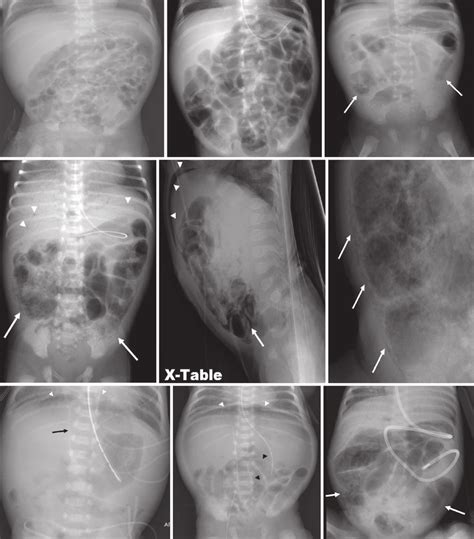

Bowel Gas Pattern

Bowel Gas RCEMLearning India